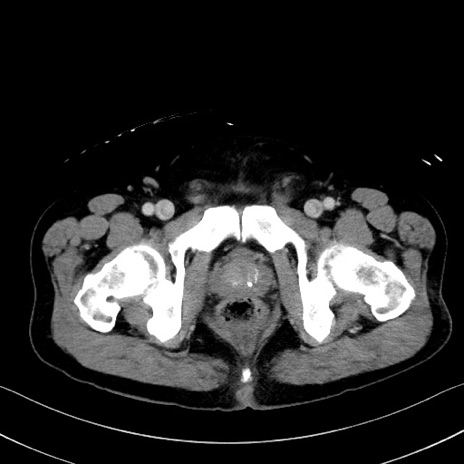

症例35(横断像)

【症例】70歳代 男性

【主訴】腹部膨満、嘔吐

【現病歴】昨日より腹部膨満感出現。本日増悪し、仙痛出現。嘔吐あり、受診。

【既往歴】糖尿病、胆摘後

【身体所見】BP 149/80mmHg、HR 74/min、BT 35.9℃、腹部:膨満、軟、圧痛なし。腸雑音減弱あり。上腹部正中切開瘢痕あり。

【データ】WBC 13500、CRP 1.72